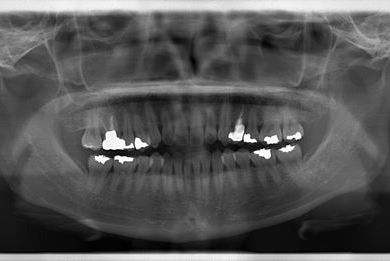

| 性別/年齢 | 女性 / 34歳 | ||||||||||||||||||||||||||||||||

| 主訴 | 以前虫歯を治療して金属を入れたところが、再び虫歯になったのか、軽くしみたり違和感がある。 | ||||||||||||||||||||||||||||||||

| 治療方針 | セラミック治療にて、審美的回復を行う。 | ||||||||||||||||||||||||||||||||

| 治療内容 | メタルボンドセラミッククラウン1本(メタルボンド用土台1本) | ||||||||||||||||||||||||||||||||

| 総治療費 | 125,685円 | ||||||||||||||||||||||||||||||||

| 治療期間 | 3ヶ月 |